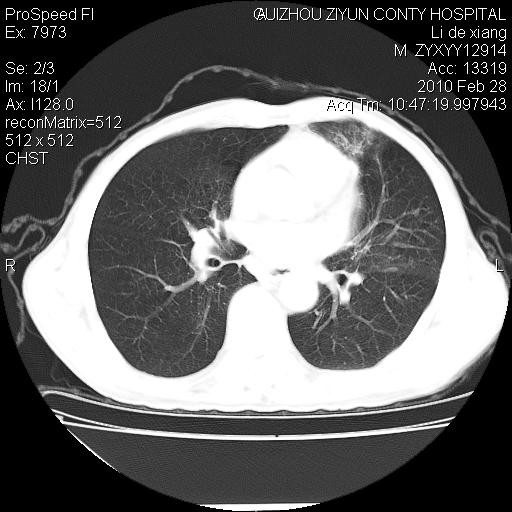

标题: CT24776:男 71Y 咳嗽咳痰胸痛两月,伴声音嘶哑。 [打印本页]

标题: CT24776:男 71Y 咳嗽咳痰胸痛两月,伴声音嘶哑。

左侧中央型肺癌伴左肺上叶阻塞性肺炎及节段性不张可能性大,建议纤支镜检查!

左肺门部肿块,伴左上肺斑块影,周边模糊,支持左肺中央型肺癌伴节段性不张及阻塞性肺炎,结合支气管镜检查。

左上叶支气管狭窄,阻塞性病变,肺门肿块,纵隔及肺门淋巴结增大,中央性肺癌

左侧中央型肺癌伴左肺上叶阻塞性肺炎及纵隔淋巴结转移